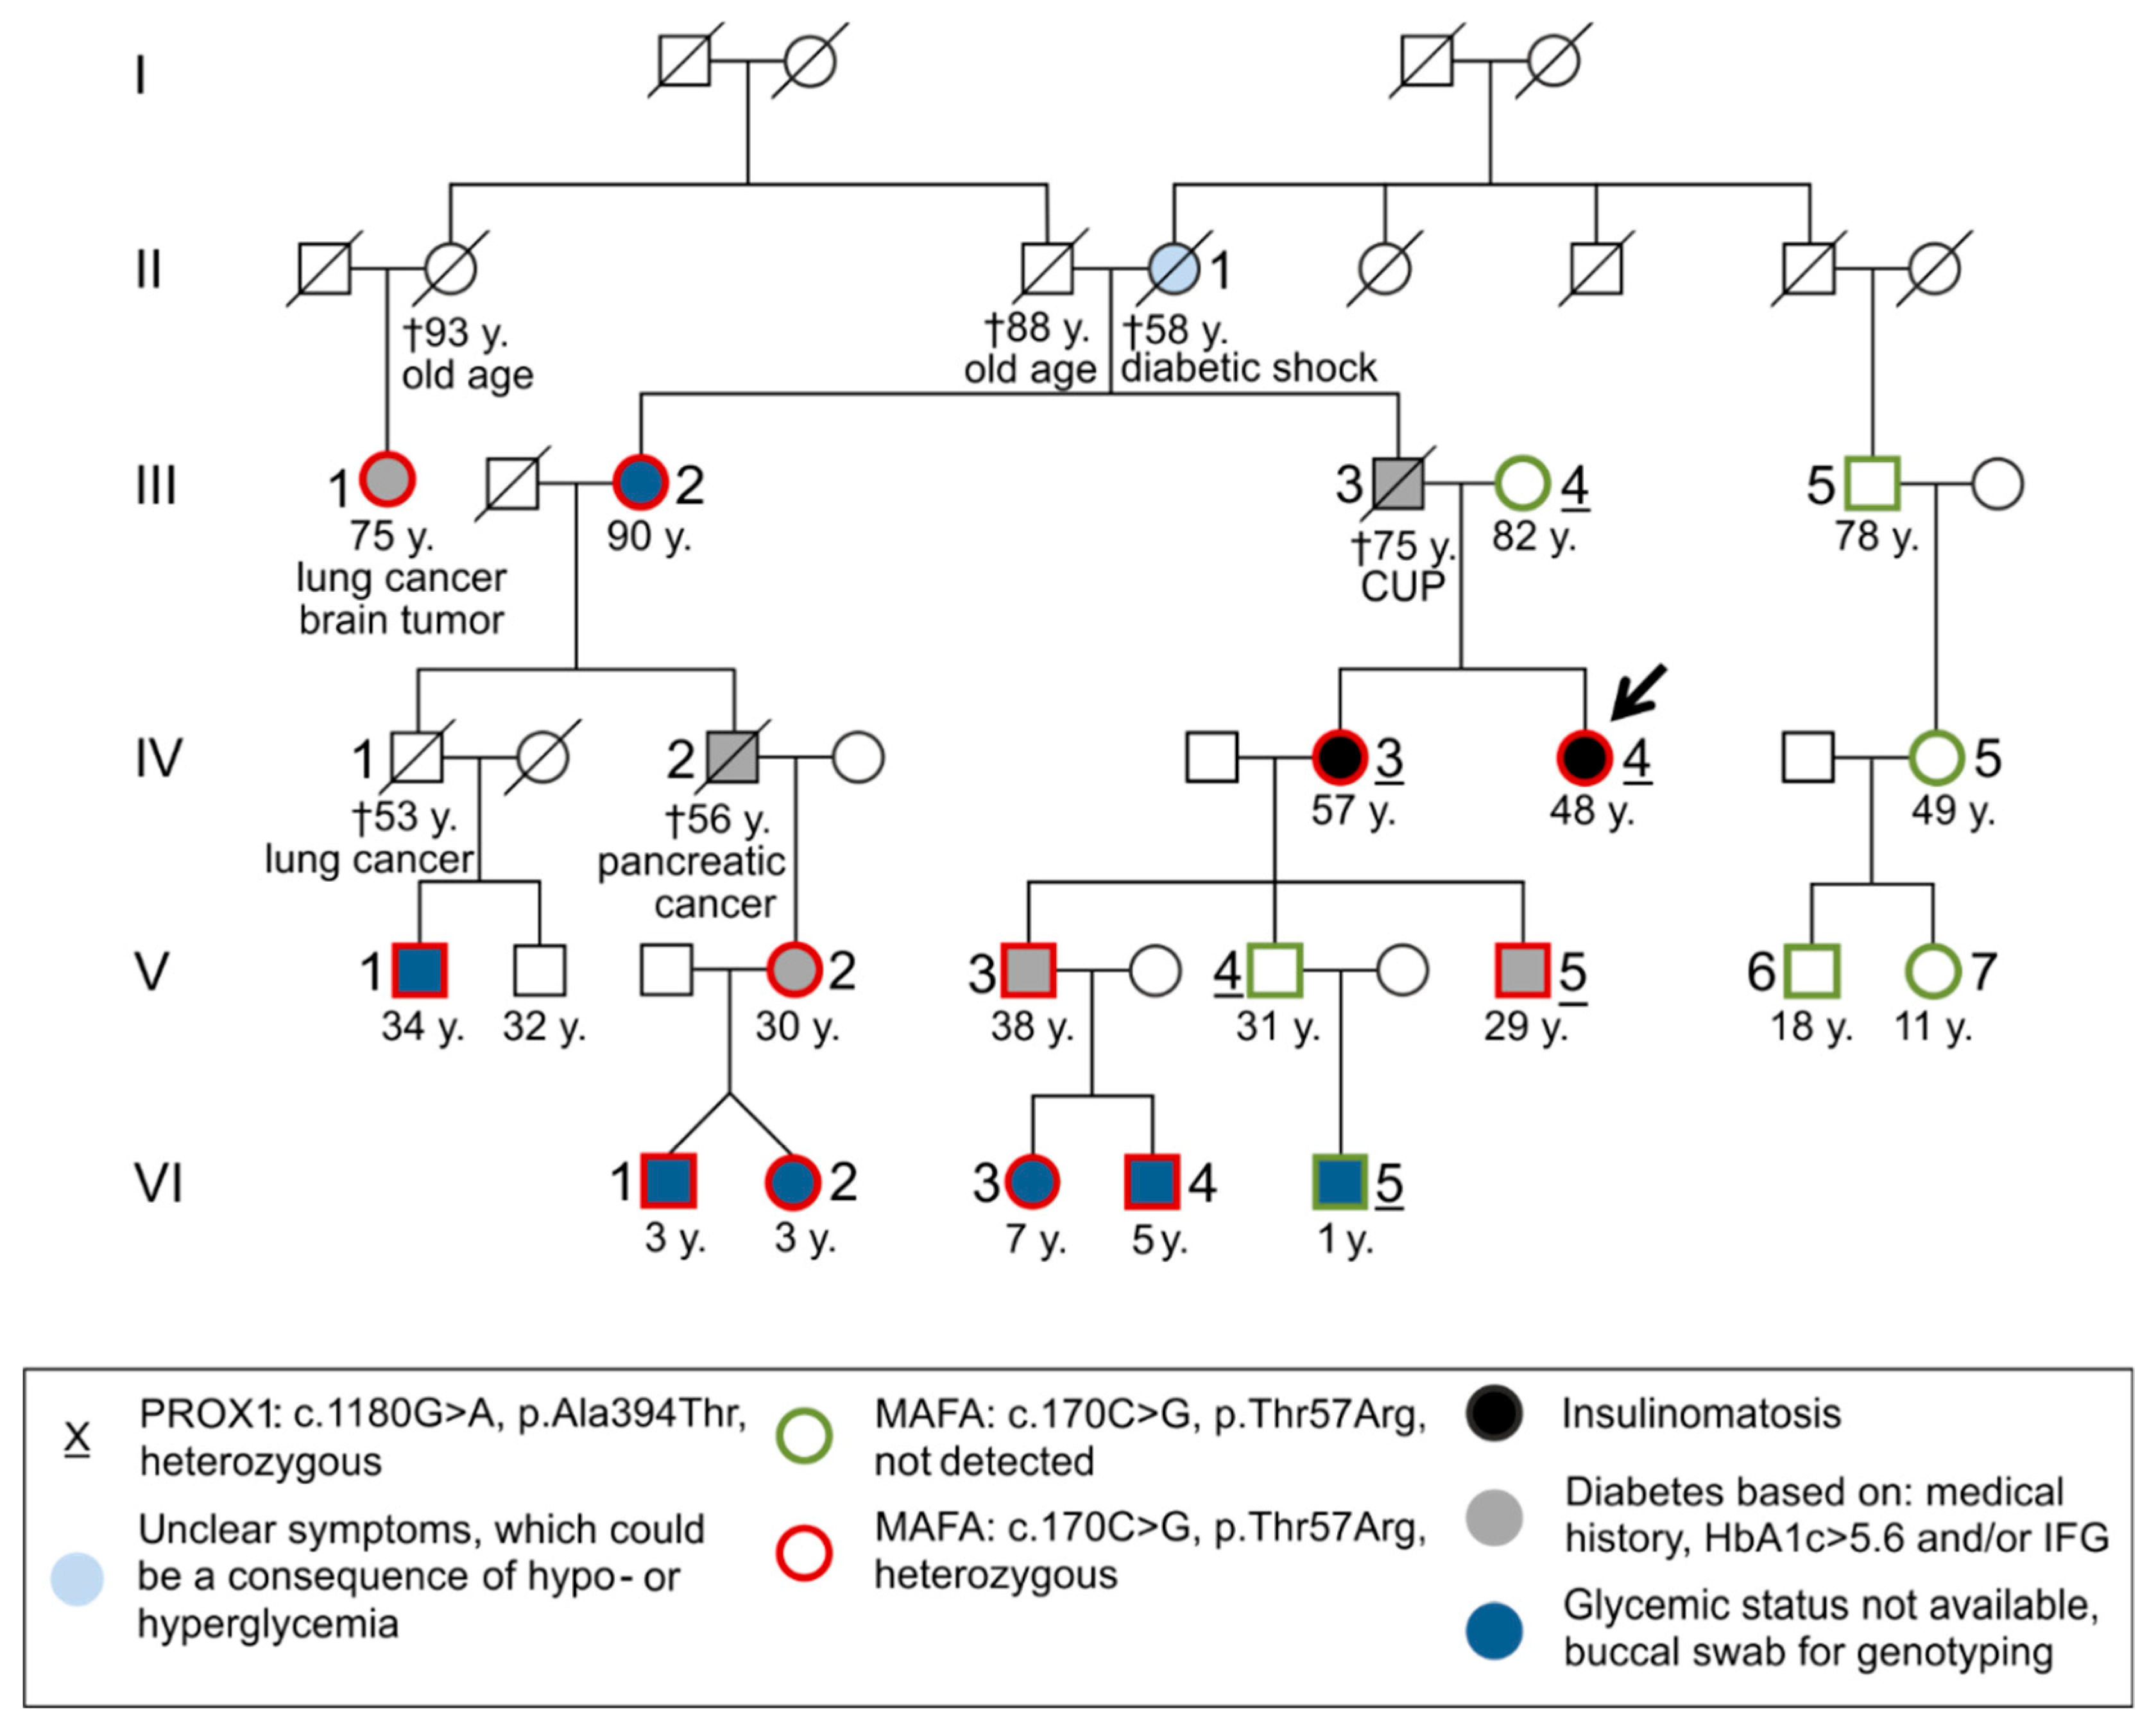

3.1. Case Report

3.1.1. Clinical Case 1; Index Patient (Female, IV4, 48 Years Old at Time of Study)

3.1.2. Clinical Case 2; Sister of Clinical Case 1 (IV3, 57 Years Old at Time of Study)

3.2. Molecular Genetic Testing

3.2.1. Molecular Genetic Testing of the Two Patients and Classification of the Detected Variants According to the ACMG Criteria

3.2.2. Molecular Genetic Testing of Asymptomatic Family Members

4. Discussion